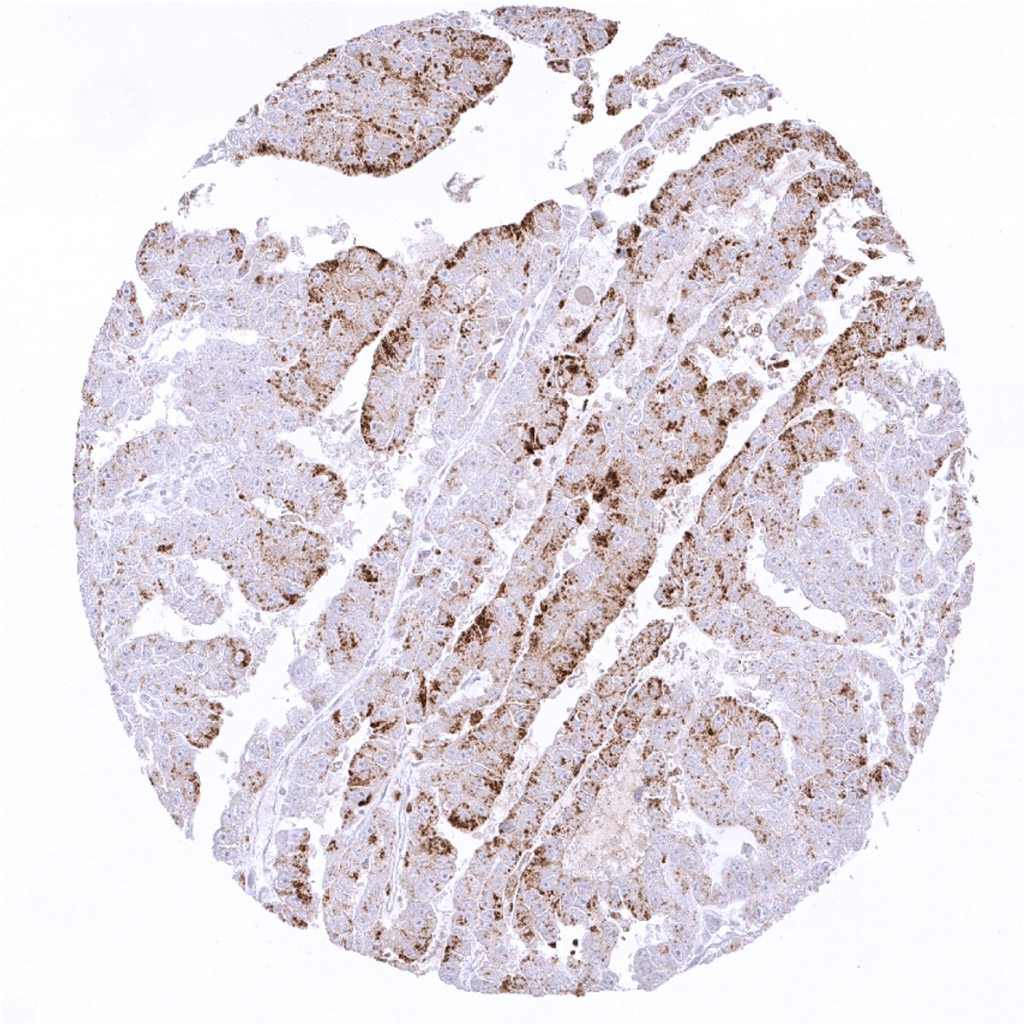

Lung- Strong Napsin A immunostaining in an adenocarcinoma of the lung.

Lung- Strong Napsin A positivity of an adenocarcinoma of the lung.

Lunge- Moderate to strong Napsin A positivity in an adenocarcinoma of the lung.

Lung- Adenocarcinoma of the lung with moderate to strong Napsin A immunostaining.

Lung- Adenocarcinoma of the lung with strong Napsin A positivity.